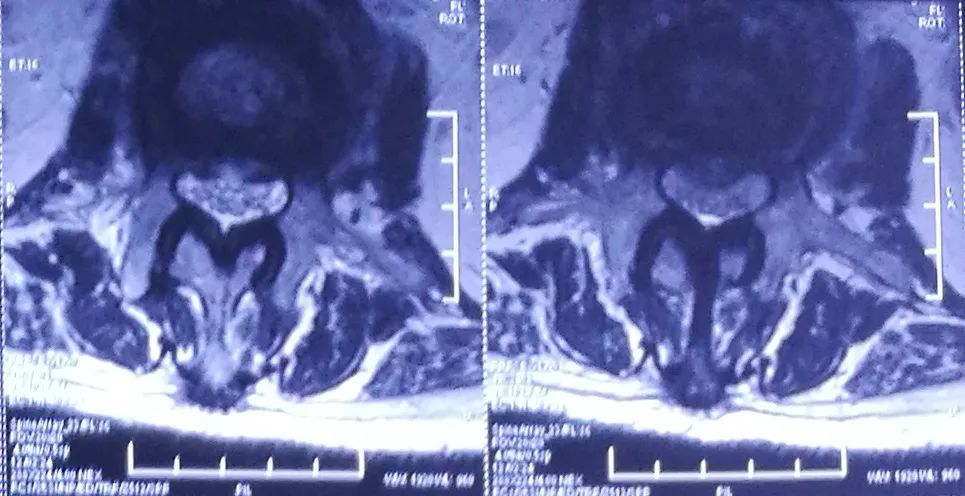

术前MRI

术后2周MRI

术前

术后2周